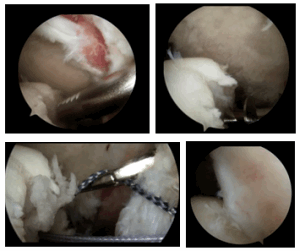

Основываясь на комплексном обследовании пациента мы применяем ту или иную хирургическую методику лечения нестабильности плечевого сустава (привычного вывиха). На настоящий момент наиболее широкое применение имеют 2 типа операций: артроскопия плечевого сустава и артроскопическое восстановление капсульно-связочного аппарата (повреждение Банкарта) при помощи якорных фиксаторов и костно-пластическая операция Латарже. В случае отсутствия значительного костного дефекта суставного отростка лопатки выполняется артроскопия плечевого сустава и стабилизация — восстановление повреждения Банкарта.

В случае наличия сопутствующего повреждения Хилл-Сакса выполняем манипуляцию «реимплиссаж», когда в зону дефекта фиксируется сухожилие подостной мышцы.

Рисунок: Артроскопия плечевого сустава: Этапы процедуры «ремплиссаж».

В случае выраженного дефицита костной структуры суставного отростка лопатки выполняем костно-пластическую операцию Латарже по транспозиции клювовидного отростка. Операцию выполняется как открыто — через небольшой разрез кожи 6-8 см по передней поверхности плечевого сустава, так и артроскопически (артроскопическая операция Латарже).